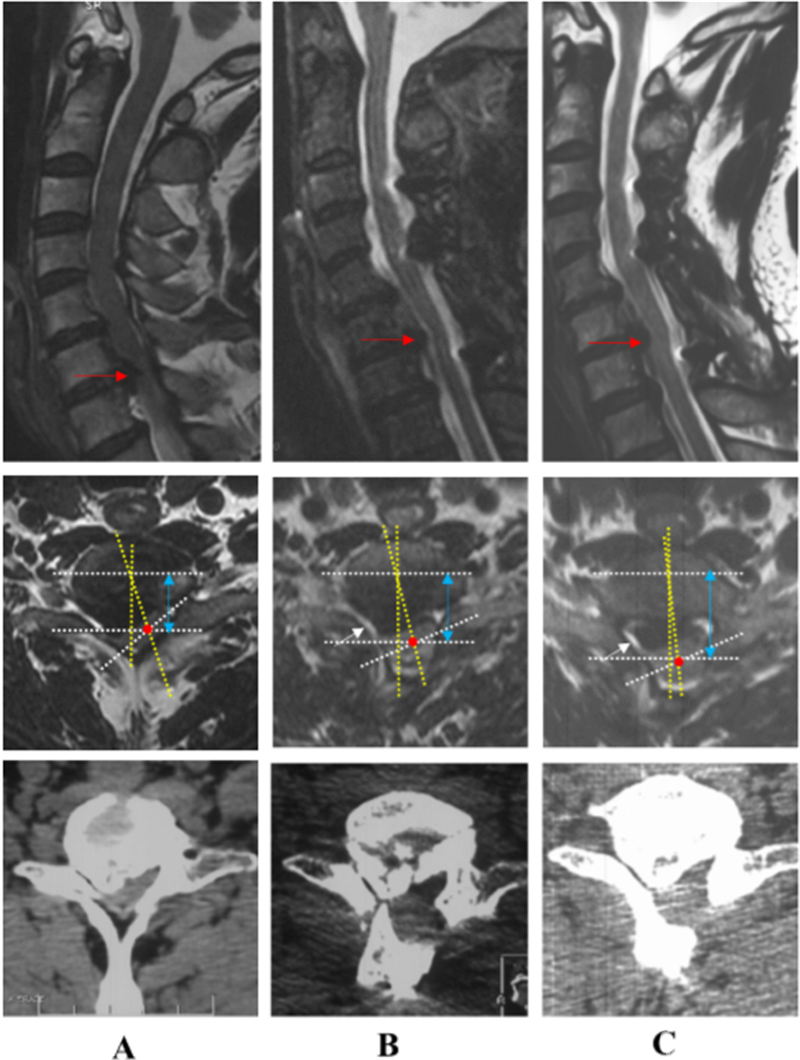

典型病例:刘某,女性,69岁,因“四肢麻木、疼痛,伴行走不稳、排尿无力1年,加重1月”,保守治疗无效。术前MRI显示C2 – C7脊髓明显受压,脊髓曲度变直,脑脊液带消失,C2-C7后纵韧带骨化,术前脊髓旋转和偏移角分别为36.3°和14.2°术前JOA评分为9。

在海军军医大学附属长征医院行ACAF治疗(手术节段C2-C7),脊髓减压彻底,脊髓旋转和偏移角显著变小。末次随访时,脑脊液、脊髓面积恢复良好,脊髓旋转和偏移几乎接近0°,由于脊髓横截面面积和位置恢复,脊髓中心前移1mm,恢复原位,JOA评分提高到15分,改善率为75%。脊髓减压彻底,神经功能改善优异,且未发生颈5神经根麻痹。

患者男性,46岁,主诉“双上肢麻木、无力、疼痛5年,加重1月”术前MRI显示C5-C7脊髓受压,骨化物压迫平面的脊髓旋转和偏移角分别为39.6°和17.4°。

在海军军医大学附属长征医院行C3-C7节段椎管成形术,脊髓间接减压但不完全,脊髓旋转和偏移角分别变为23.5°和13.6°,且术后出现右上肢不能上抬(C5神经根麻痹),原因可能是C4/5水平的右侧神经根由于偏右侧型骨化物压迫受到牵拉,加上脊髓向后漂移,麻痹侧神经根可能受到更大的张力。末次随访时,脑脊液、脊髓面积仍恢复较差,脊髓旋转和偏移角仍较大,脊髓向后漂移3.0mm,JOA评分由术前9改善到12,改善率为37.5%,仍残留部分麻木疼痛症状。